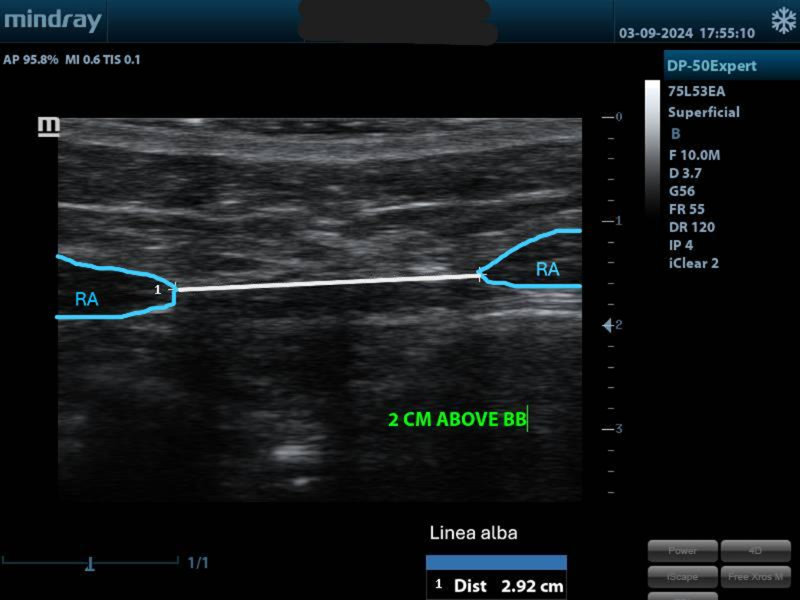

The tummy check can be very interesting especially in post-partum, after abdominal surgery or if you suspect having a diastasis recti (separation between your abs).

We will: